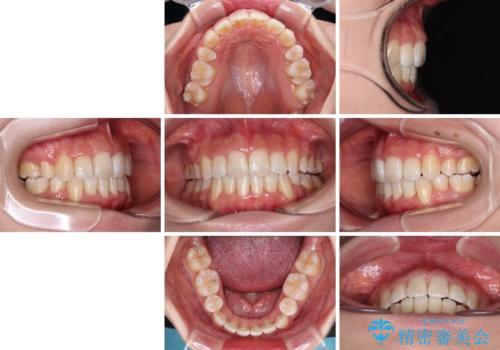

デコボコと出っ歯 抜歯矯正でスッキリとした口元に

デコボコの解消で歯が磨きやすくなり、抜歯矯正により口元の突出感が大幅に改善され、スッキリした口元になりました。